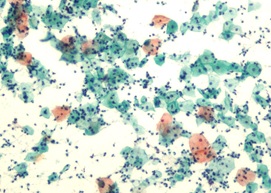

病理検査

手術や生検で採取した臓器や組織を染色、鏡検することで疾病の確定診断などを行います。

- 組織診断

- 細胞診断

- 病理解剖 など

【婦人科の細胞診画像】